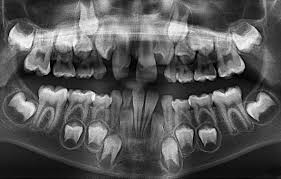

Il est un fait reconnu que les fluorures fortifient la structure dentaire, d’ou l’importance de leur ingestion durant la période de formation des dents, nottament des dents définitives.